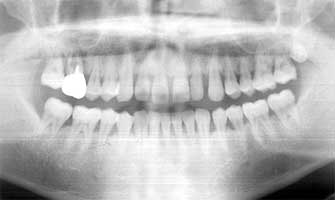

Fig. 13 Ms F 16 years old at the time of first medical examination. Woman

I regard this case to that of juvenile gum disease because there is high deposition of dental calculus and a high possibility of destruction of the alveolar bone.

Ms F 16 years old at the time of the first medical examination. Woman (Fig. 13-14)

She has undergone gingivitis treatment two years ago. However a lot of tartar of the edge of the gum was found on her teeth at the time of first medical examination. Her 5 year older sister already had a tooth in the final stage of gingivitis. Ms F therefore had the strong possibility of also developing to the final stage. Taking note of this I believed her to be of juvenile gum disease. As a result of consistently continuing to remove the tartar her tendency to develop gingivitis has not occurred even 17 years later. Even her older sister who lost a tooth to gingivitis, 16 years later has maintained and retained all other teeth.